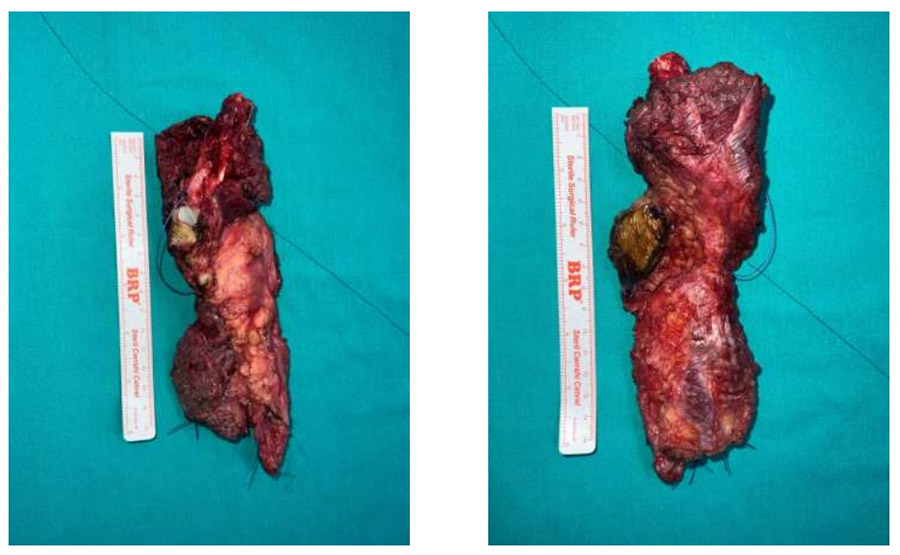

Ameliyat Esnası: Çıkarılan tümör dokusunun klinik görüntüsü